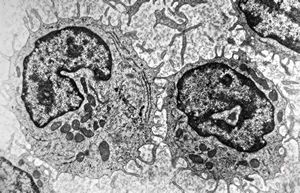

F,51y. | blood - chronic lymphatic leukemia … prolymphocyte

F,72y. | blood - lymphoplasmocellular leukemia